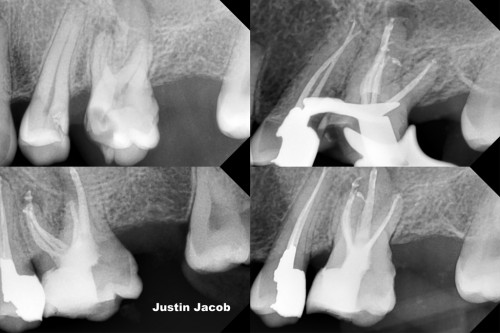

Sealer dynamics helped not to leave an untreated canal in Mesio-buccal root

Justin Jacob